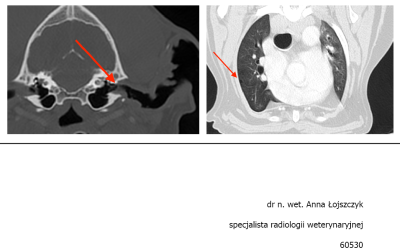

Maxiu jest po pełnej diagnostyce.

Zmiana okazała się włókniakomięsakiem :cry:

Jak pisze Pani Dorota:

Aktualnie nie tracimy czasu i Maks przyjmuje chemię metronomiczną. Do tego rozważamy operację, którą zalecił chirurg onkolog Anna Rajska Krysa z przychodni Bemowo Wet - tam robiliśmy wszystkie badania i tam są w miarę dostępne terminy jesli chodzi o wizyty, dlatego zdecydowaliśmy się na leczenie w tym miejscu.

Nie jesteśmy jeszcze zapisani na zabieg ponieważ taka operacja to duże ryzyko dla psa w tym wieku, w dodatku umiejscowienie guza jest dość kłopotliwe, bo chirurg na pewno będzie musiał zachować margines przy wycięciu i usunąć część kości z nosa :( i szukam oczywiście jeszcze innych opcji i miałam nadzieję, że jest inny sposób, ale wygląda na to, że niestety operacja jest nieunikniona.

Obraz TK 1.jpg

Plik ściągnięto 6 raz(y) 29.5 KB

Obraz TK 2.PNG

Plik ściągnięto 7 raz(y) 344.31 KB